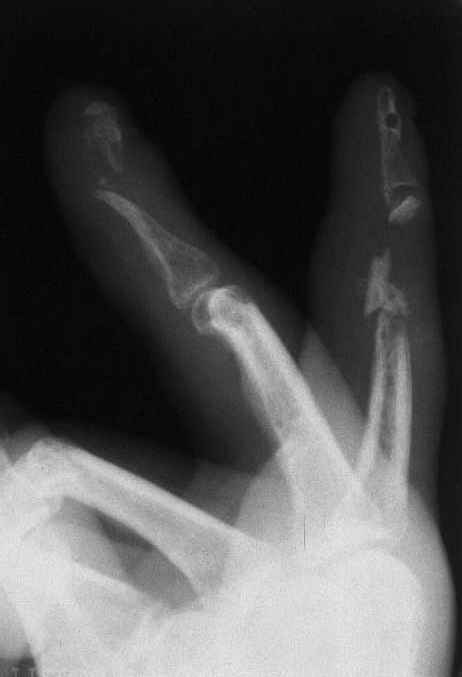

33 yo male motocross rider crashed after a jump sustaining isolated bilateral femur fxs, R side with a basicervical femoral neck and ipsilateral mid-distal 1/3 shaft, L side with a subtroch/prox 1/3 femur fx. Pt was HD stable, no LOC, GCS - 15, No other injuries, spines cleared.

Implants ­ plenty of opinions exist for the right side...some would use neck screws anteriorly after reduction, then with a slender reamed locked nail

pushed in behind the neck screws for the shaft... some will advocate a recon nail for both...some will use a sliding screw for the neck then a retrograde shaft nail...some would use the sliding neck screw and a shaft plate also...lots of options.

I prefer excellent neck reduction either closed or open, screws high and low anteriorly for it, then a frail locked nail slipped in behind the neck screws for the shaft.

basicervical neck is normally treated with hip screw or cephalomedullary nail.

after perfect reduction (either closed or open) i would attempt 1 implant to treat both (i.e. TFN or Intertan). can do anything though like Dr. Routt mentioned. intertan is nice because of the rotational stability it imparts in the neck

Chip Routt listed all main options. The right proximal fracture looks closer to trochanteric. Most elegant solution would be to fix all with a single implant with minimal incisions. Long Gamma nail or any other reconstruction or proximal type nails are suitable. Technically less demanding wiuld be temporary neck pinning as is, retrograde nailing of the shaft, then final reduction and fixation of the trochanteric fracture as isolated, by DHS with 2 holes plate. Good luck.